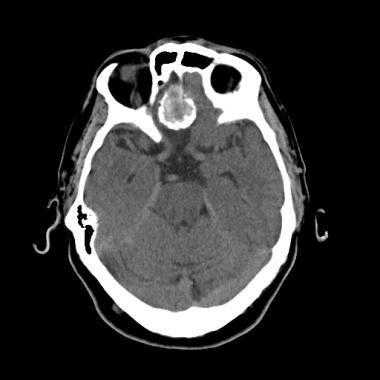

(Слева) КТ в костном окне, аксиальная проекция. Характерные инфильтративно-склеротические костные изменения в области основания черепа и яремного отверстия. Обратите внимание, что внутричерепная часть опухоли частично кальцифицирована.

2. КТ при менингиоме сонного пространства:

• КТ без контрастирования:

о При наличии псамматозных кальцификатов плотность может быть высокой

• КТ с КУ:

о Умеренное накопление контраста

о Внутренняя сонная артерия смещена кпереди

• КТ в костном окне:

о Края яремного отверстия: склеротические изменения, либо гиперостоз